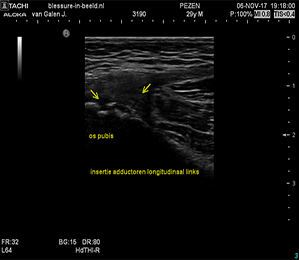

Orthopedische echografie, een blessure nader bekeken .........

Wij beschikken over mobiele echo-apparatuur met haarscherp beeld!